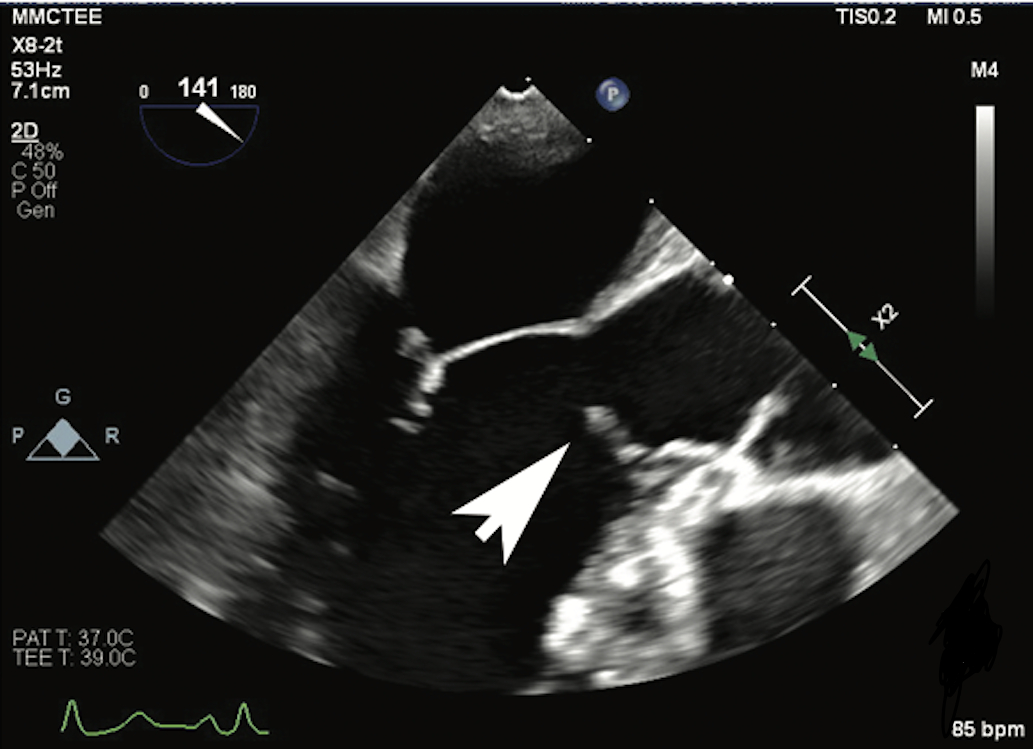

A 42-year-old female with a history of sub-aortic membrane resection 10 years ago presented to the cardiology clinic with complaints of exertional dyspnea and two episodes of syncope. She was referred to the ER, where her vitals were stable, and both her EKG and troponin levels were normal. A cardiac CT scan was performed which revealed an area of myocardial bridging involving the mid-left anterior descending artery. Transthoracic echocardiogram showed an aortic valve (AoV) peak velocity of 2.78 m/s, a peak gradient of 31 mmHg, a mean gradient of 14 mmHg and an AoV area of 2.09 cm square. There were elevated pressure gradients across the left ventricular outflow tract (LVOT) and AoV with a maximum gradient of 31 mmHg at rest. Left and right heart catheterization demonstrated normal coronary arteries, but an elevated left ventricular end-diastolic pressure of 30 mmHg was noted. The resting LVOT gradient was elevated at 20 mmHg, and post-premature ventricular contraction gradients were as high as 50 mmHg, suggesting dynamic obstruction. Subsequently, a transesophageal echocardiogram revealed a subaortic membrane in the proximal part of the LVOT (figure 1). Cardiothoracic surgery was consulted for a redo subaortic membrane resection.